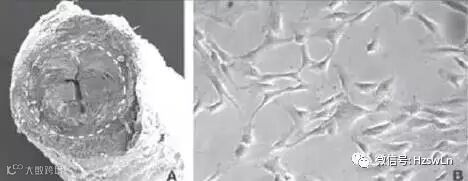

1、目前已经有实验证实间充质干细胞可定植于肺并分化为肺上皮细胞以缓解由脂多糖引起的急性肺损伤和博莱霉索引起的慢性肺损伤。而将人间充质干细胞与小气道上皮细胞共培养发现一部分间充质干细胞迅速分化为上皮细胞并回复上皮细胞单层,其他间充质干细胞直接与上皮细胞融合。最近有报道称间充质干细胞通过修复哮喘气道上皮细胞促进气道上皮重建。因而我们可以考虑凭借干细胞技术来修复气道上皮细胞,增强上皮防御能力,防止哮喘疾病进展。